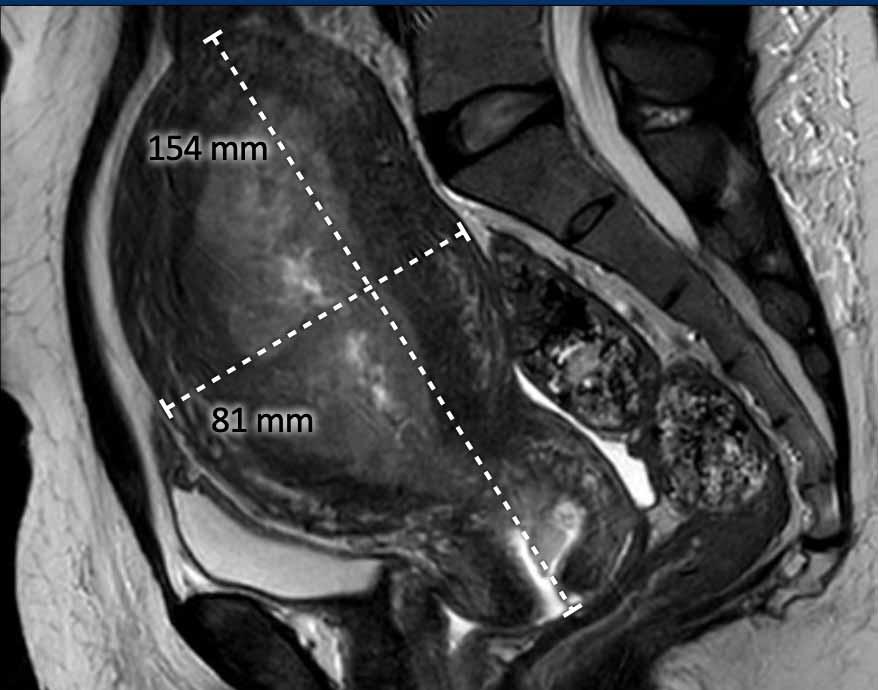

Kích thước toàn bộ tử cung

Kích thước toàn bộ tử cung là thông tin quan trọng cần báo cáo vì nó ảnh hưởng đến chiến lược phẫu thuật, bao gồm lựa chọn đường vào qua âm đạo, nội soi ổ bụng hay mổ mở qua thành bụng.

Nếu kích thước tử cung quá lớn (ví dụ: >10 cm), đây sẽ là chống chỉ định để thực hiện phẫu thuật qua âm đạo hoặc nội soi ổ bụng.

Kích thước tử cung thường được đo trên mặt phẳng đứng dọc (sagittal) theo 2 chiều: đầu-đuôi (bao gồm cổ tử cung) x trước-sau (hình).